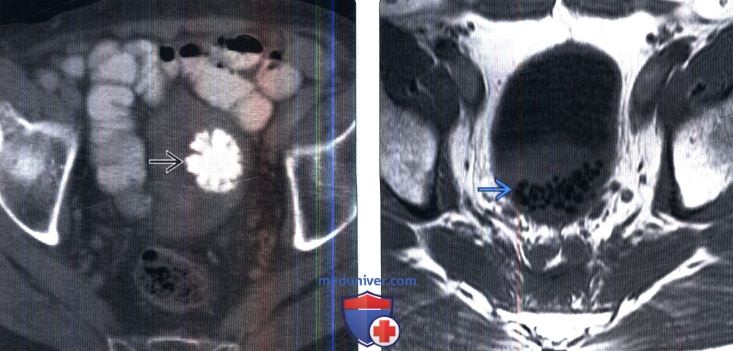

Изображения КТ конкрементов мочевого пузыря